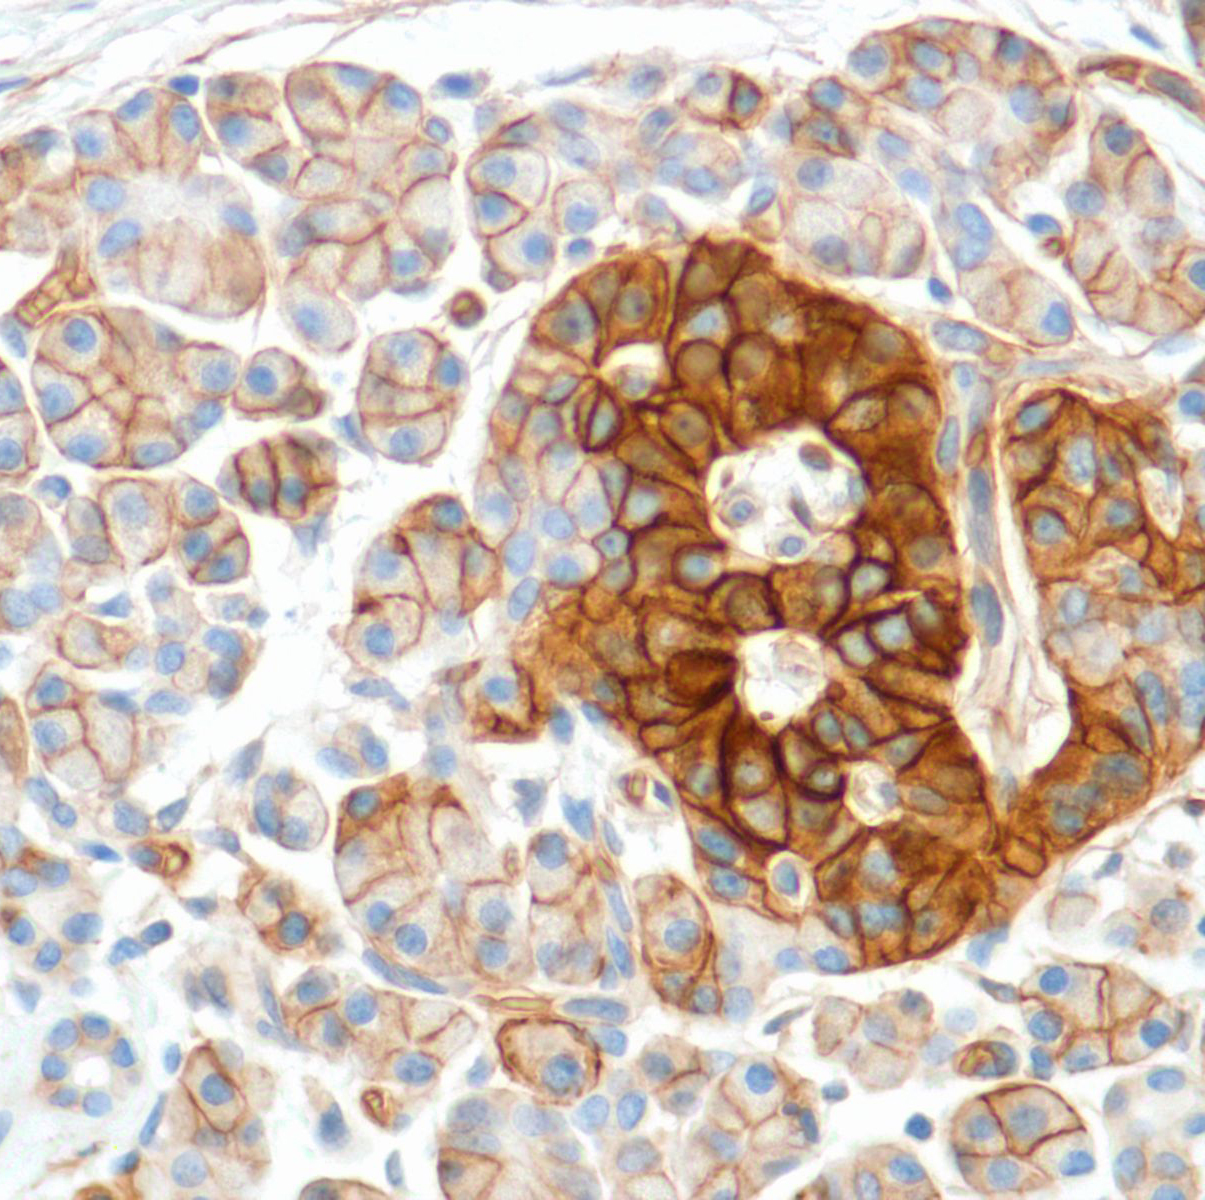

hENT1

Human equilibrative nucleoside transporter 1 (hENT1) is a member of the equilibrative nucleoside transporter family. It is a transmembrane glycoprotein that localizes to the plasma and mitochondrial membranes and mediates the cellular uptake of nucleosides from the surrounding medium. The protein is sensitive to inhibition by nitrobenzylthioinosine (NBMPR). It is considered as a drug carrier. Nucleoside transporters such as hENT1 are required for nucleotide synthesis in cells that lack de novo nucleoside synthesis pathways, and are also necessary for the uptake of cytotoxic nucleosides used for cancer and viral chemotherapies.